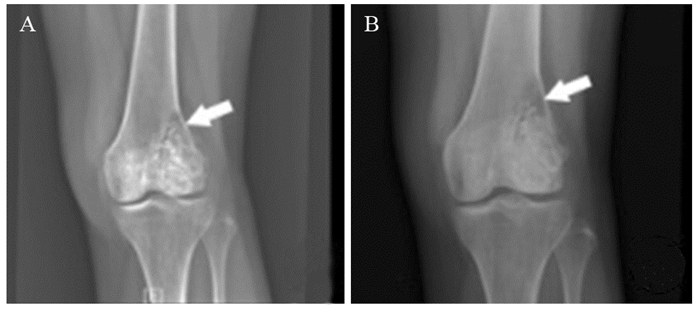

CampanacciⅠ级骨巨细胞瘤行单纯刮除术后均无复发;CampanacciⅡ级骨巨细胞瘤行单纯刮除术、扩大刮除术及瘤段或分块切除术后复发率分别为17.3%(23/133)、7.1%(7/98)、0(0/10);CampanacciⅢ级骨巨细胞瘤行单纯刮除术、扩大刮除术及瘤段或分块切除术后复发率分别为28.1%(18/64)、6.9%(6/87)、4.5%(2/44),见图 1~3。两两比较三种手术后复发率的差异,结果显示Ⅲ级骨巨细胞瘤单纯刮除术后复发率明显高于扩大刮除术(P < 0.001)以及瘤段或分块切除术(P=0.002),差异有统计学意义,而扩大刮除术与瘤段或分块切除术后复发率差异无统计学意义(P=0.885);Ⅱ级骨巨细胞瘤三种手术后复发率的差异无统计学意义(P > 0.017),见表 3。

![]() 图 2 骨巨细胞瘤单纯刮除术后复发病例CT结果Figure 2 CT scan of one recurrence case with giant cell tumor of bone after simple excochleationA 24-year-old male with giant cell tumor of bone in the left distal tibia suffered tumor recurrence 3 months after anterior approach surgery with simple excochleation and inactivation of bone graft because of exposure difficulty in the internal posterior side and insufficient scraping range; A: before operation; B: 3 months after surgery

图 2 骨巨细胞瘤单纯刮除术后复发病例CT结果Figure 2 CT scan of one recurrence case with giant cell tumor of bone after simple excochleationA 24-year-old male with giant cell tumor of bone in the left distal tibia suffered tumor recurrence 3 months after anterior approach surgery with simple excochleation and inactivation of bone graft because of exposure difficulty in the internal posterior side and insufficient scraping range; A: before operation; B: 3 months after surgery![]() 图 3 骨巨细胞瘤大块切除术后病例影像学检查结果Figure 3 Imaging results of one case with giant cell tumor of bone after block resectionA 26-year-old female with giant cell tumor of bone in the 1st sacrum found no evidence of recurrence 53 months after surgery with the whole block below the 3rd sacrum resected and nerve-retained enlarged excochleation above the 3rd sacrum. A, B: preoperative CT scan; C: preoperative MRI; D: X-ray 53 months after surgery; E: CT scan 53 months after surgery表 3 手术方式与骨巨细胞瘤复发率的关系Table 3 Relationship between operation method and recurrence rate of giant cell tumor of bone